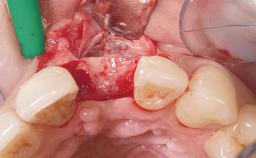

A 42-year-old female patient was referred to our clinic at the School of Dentistry of the University of São Paulo in November 2004, presenting a deficient restoration in the upper left central incisor. The clinical examination revealed no gingival retraction or any signs of gingival inflammation and, therefore, previous periodontal treatment was not considered. The patient presented a high lip line at full smile and a thin tissue biotype. This combination characterized a high-risk situation from an anatomic point of view, which required careful preoperative planning and cautious surgical execution.

Placement Protocol Immediate implant placement

Socket Integrity Sufficient, with intact bone walls

Bone Volume Sufficient, with intact walls